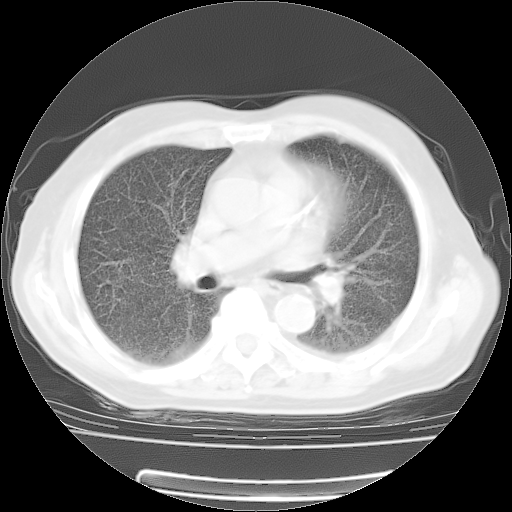

4月28日肺部CT——再次出现类似去年5月9日——透光度降低,(影像科认为)“间质性”改变。

1221483 1 .bmp

1221483 2 .bmp

1221483 3 .bmp

1221483 4 .bmp

1221483 5 .bmp